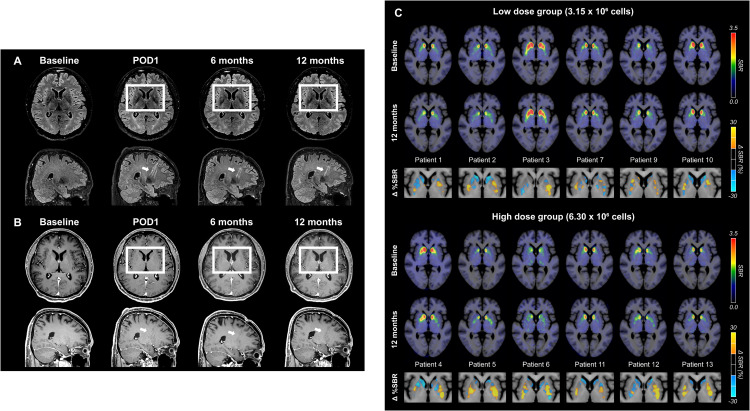

四、關鍵影像學證據:影像檢查證實細胞存活并發揮作用

影像學檢查為上述臨床改善提供了客觀的生物學證據:

術后MRI顯示,移植區域未出現腫瘤或明顯炎癥反應,細胞被準確植入殼核目標區域,初步證明手術和細胞定位的安全性與可控性。

更關鍵的證據來自多巴胺轉運體PET成像。與基線相比,后背側殼核區域的DAT信號在高劑量組明顯升高,且這種變化與患者停藥狀態下的運動改善程度呈顯著相關。這意味著,影像學上觀察到的多巴胺能功能增強,與臨床癥狀的改善方向一致。(圖6)

這些結果共同表明:移植的多巴胺祖細胞不僅在腦內存活,而且在關鍵運動環路中實現了功能性整合,并與實際運動改善相對應。